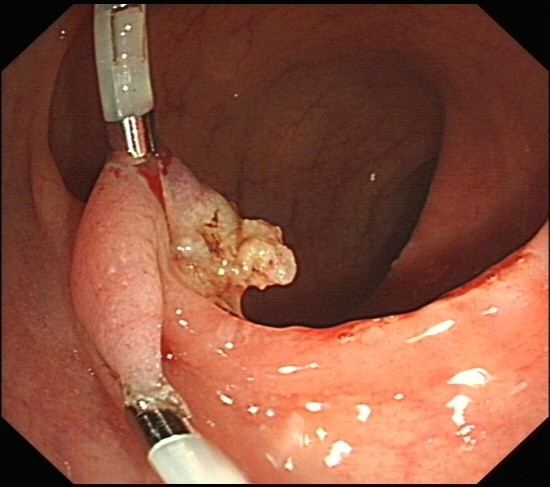

直肠部分有6cm的息肉表面不光滑